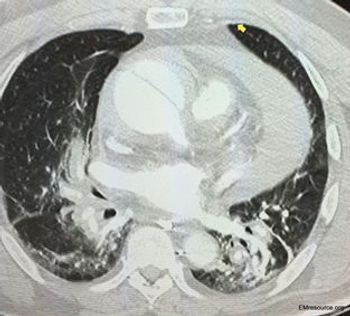

A man with a history of hypertension had syncope and felt “sweaty.” Chest x-ray was normal. What’s your next test?